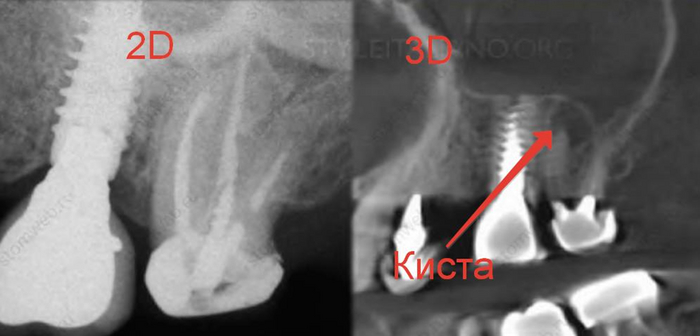

После того, как пациент сделает нормальный трехмерный снимок, с вероятностью 90% мы будем наблюдать один из подобных примеров.

Панорамный снимок- двухмерный

Компьютерная томография- трехмерный

Как вы уже догадались при получении двухмерного изображения трехмерного объекта, его структуры будут накладываться друг на друга. Так как рентген-диагностика заключается в анализе разницы плотности слоев, что выражается на снимках в виде различных оттенков серого, то более плотные слои(белые) могут запросто перекрывать менее плотные(черные), из-за чего точность этой диагностики снижается.

Компьютерная томография «нарезает» объект послойно, позволяя увидеть все структуры под каким угодно углом без искажений. Таким образом мы сможет поставить максимально точный диагноз, определить более точный прогноз зуба, определить расположение будущих и уже установленных имплантатов, определить расположение гайморовой пазухи и нижнего альвеолярного нерва при удалении сложных зубов, определить расположение корней, определить количество каналов в корнях….можно продолжать долго.

Вот ещё примеры.